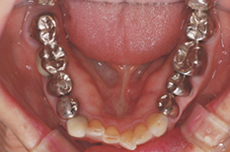

銀歯が錆びて黒くなってます

銀歯は審美面、健康面でオススメできません

先程も申し上げたように、いわゆる銀歯といわれる金銀パラジウム合金は保険制度の経済的な理由から選択された素材です。良いところは保険が効くので「安い」ということだけです。

審美的に見ると、銀歯は全く自然でないのでオススメできません。

それは奥歯の詰め物であってもです。

![]() |